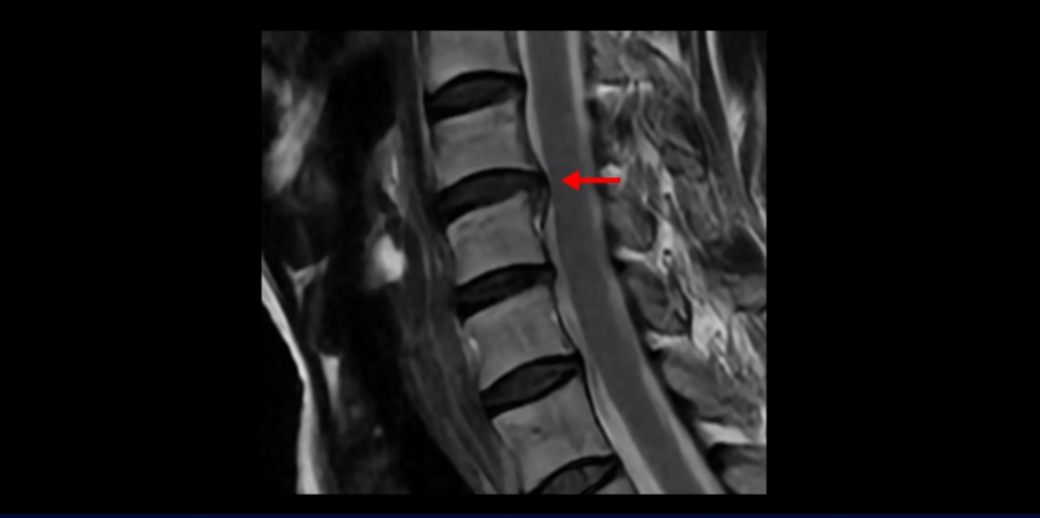

이분 MRI를 보면 세 마디의 퇴행성 목디스크가 있습니다. 4번 5번, 5번 6번과 6번 7번이 세 마디인데

디스크 파열은 4번 5번이 제일 심합니다.

중앙 오른쪽으로 수핵이 밀려 나와있고 밑으로 흘러 내려가 있습니다.

그런데 이 환자분의 방사통은 왼쪽 어깨와 팔입니다. 그래서 이 4번 5번 디스크 파열은 왼쪽 방사통의 원인이 아닌 걸로 보입니다. 6번 7번을 보면 디스크가 왼쪽으로 밀려 나와 있고, 뼈도 자라나 있습니다.